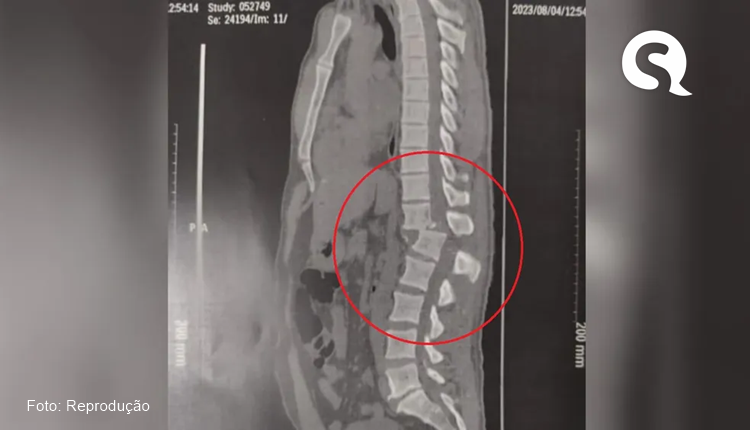

O ex-motorista de aplicativo sofreu uma lesão gravíssima na coluna depois que um aparelho com 150kg de carga caiu sobre os ombros dele. O acidente aconteceu em Juazeiro do Norte, no Cariri cearense, no último dia 4 de agosto.

No dia seguinte, ele precisou passar por uma cirurgia de urgência, que durou cerca de quatro horas. A avaliação dos médicos, logo após o procedimento, era que Regilânio tinha 1% de chance de voltar a andar. Ele não tinha sensibilidade da cintura para baixo, mas recuperou após as sessões de fisioterapia que iniciou após o acidente.